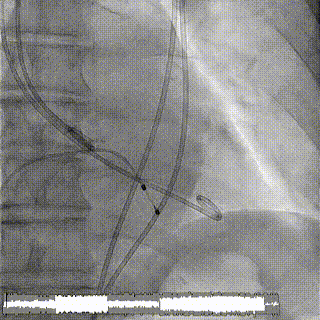

术中影像

1.主动脉根部造影,可见大量反流

2.输送系统过主动脉弓

3.输送系统造影定位

4.释放瓣膜

5.瓣膜完全释放

6.最终造影,反流消失